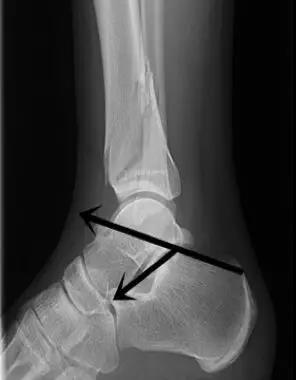

踝关节

- 结节关节角:是在跟骨后关节面最高点与跟骨结节间做一连线,再在跟骨前端背侧最高点与后关节面最高点做另一连线,连线相交成角,称为结节关节(Böhler角)。

- 正常值:25°~40°

- 临床意义:跟骨结节关节角减小,提示跟骨骨折或扁平足;跟骨结节关节角增大,提示弓形足。